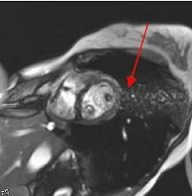

Figure 5. Off-resonance effects on cardiac FIESTA

- The enhanced FIESTA sequence significantly reduces off-resonance effects that are sometimes encountered when the correct center frequency of a cardiac image is difficult to obtain. The following enhancements in the 2D FIESTA prescan technique result in a significantly improved spectrum:

- 2D Gated FIESTA sequences that are prescribed in a single slice group have a unique prescan and shimming technique. Cardiac FIESTA imaging often results in off-resonance artifacts when the center frequency is incorrectly obtained. These artifacts appear as inhomogeneous areas within the blood pool and as ghosting across the image. They are more prominent in areas of fast or turbulent blood flow.